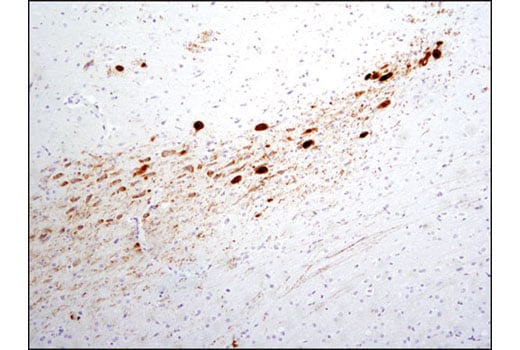

Immunohistochemical analysis of paraffin-embedded mouse brain using Phospho-Tyrosine Hydroxylase (Ser31) (D6I9V) Rabbit mAb.

Immunohistochemistry Image 1: Phospho-Tyrosine Hydroxylase (Ser31) (D6I9V) Rabbit Monoclonal Antibody